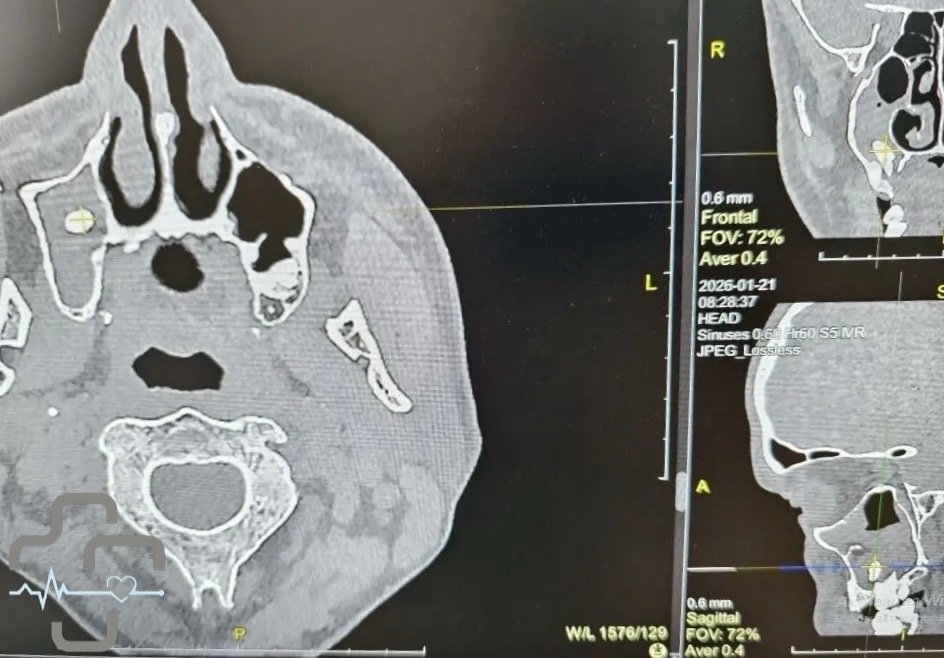

В Орске мужчина обратился в больницу с жалобами на затрудненное дыхание. Оказалось, что в его носовой пазухе оказался зуб. Об этом сообщили на странице во "ВКонтакте" городской больницы Орска. Выяснилось, что ранее мужчина удалил зуб. В медучреждении объяснили, что такое случается, когда при удалении зуба происходит нарушение целостности костной перегородки, отделяющей зубной ряд от носовой пазухи, из-за чего зуб или его фрагмент могут сместиться в пазуху. У пациента зуб проник так глубоко, что это повлияло на дыхание. Благодаря профессионализму врача и применению современной эндоскопической стойки, удалось аккуратно и точно извлечь зуб. - отмечается в сообщении. После проведения успешной операции зуб был подарен мужчине.